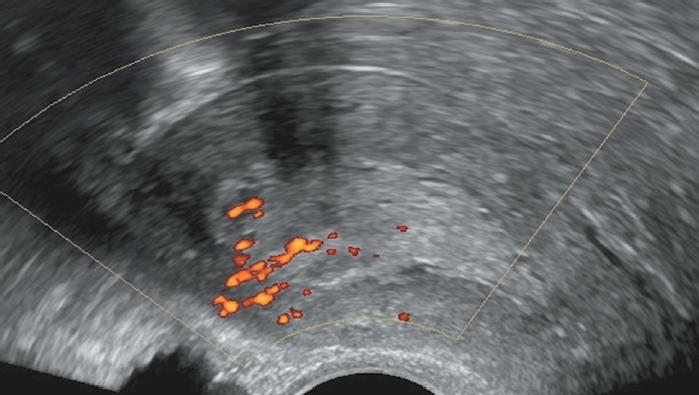

Помимо толщины эндометрия с помощью УЗИ необходимо оценить и отразить в протоколе исследования структуру, васкуляризацию, жесткость и наличие жидкости в полости матки. В случае тамоксифен-индуцированных изменений эндометрий аваскулярный, мягкий в режиме соноэластографии, жидкость в полости матки отсутствует (рис. 2). Из-за развития тамоксифен-индуцированной стромальной гиперплазии эндометрия корреляция между толщиной эндометрия и его патологическими изменениями у бессимптомных пациенток низкая, вследствие чего скрининговое вагинальное УЗИ и/или биопсия эндометрия не рекомендуются [25–27]. Перед началом терапии тамоксифеном целесоообразно выполнение трансвагинального УЗИ органов малого таза, так как пациентки с исходной патологией эндометрия имеют больший риск развития тамоксифен-индуцированного РЭ.

Рис. 2. Пациентка В. Постменопауза 5 лет. Прием тамоксифена — 3 года 8 месяцев. Толщина эндометрия — 10 мм. При ЦДК — эндометрий аваскулярный. При эластографии — второй (мягкий) тип эластичности. Кистозная атрофия эндометрия

Fig. 2. Patient V., 5 years postmenopausal, after 3 years 8 months of Tamoxifen therapy. Endometrial thickness = 10 mm. Endometrial tissue is avascular (colour Doppler imaging) and soft (elastography). Cystic endometrial atrophy